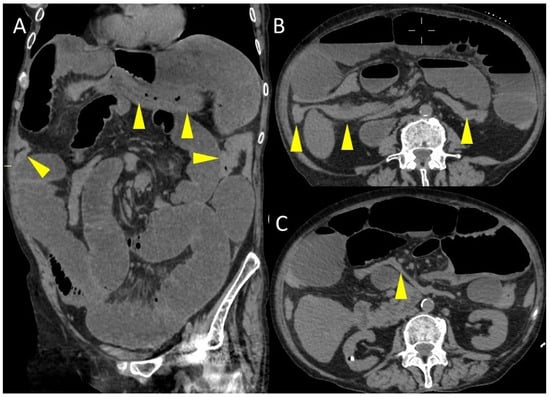

Figure 3. Coronal (A) and axial (B,C) CT images. The yellow arrowheads indicate the colon, which is collapsed throughout its course.